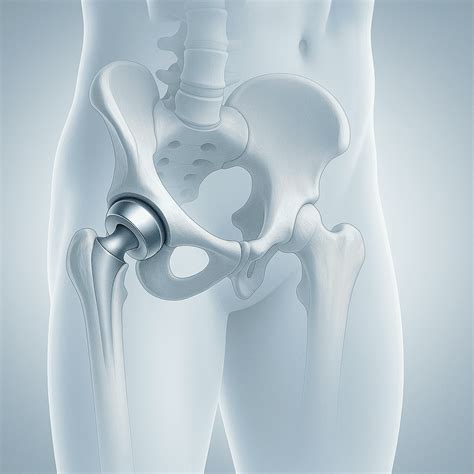

Illustration of hip resurfacing vs total hip replacement

At its core, Hip Resurfacing Surgery is a bone-conserving procedure. During the operation, the surgeon does not remove the femoral head (the ball of the hip joint). Instead, the damaged surface of the ball is carefully trimmed and reshaped. A metal cap is then fitted over the reshaped bone, and a matching metal cup is placed into the socket of the pelvis. This metal-on-metal design is intended to withstand the rigors of high-impact activity better than traditional polyethylene-based implants.

The primary advantage of this approach is that it maintains the anatomy of the hip, which can make future revision surgeries—if ever needed—much simpler. Because less bone is removed, the structural integrity of the femur remains largely intact, allowing for a more stable and "normal" feeling hip joint post-recovery.